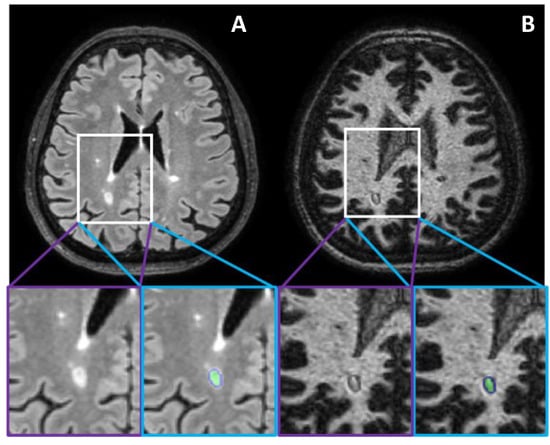

- White-matter selective DIR, FLAIR and T1w sequences were obtained using PAchieva scanners (, Philips Healthcare, Best, The Netherlands) at both MRI field strengths. For the sake of clarity, the WM-DIR sequence used in this work serves the same purpose as the GM-DIR sequence used in [8]. The DIR sequence is usually used for cortical lesion load assessment that involves mainly the GM tissue, whereas the WM-DIR sequence enhances the WM tissue and permits the detection of DRLs. Therefore, we will refer to WM-DIR in the forthcoming paragraphs.

- Tillema, J.-M.; Weigand, S.D.; Dayan, M.; Shu, Y.; Kantarci, O.H.; Lucchinetti, C.F.; Port, J.D. Dark Rims: Novel Sequence Enhances Diagnostic Specificity in Multiple Sclerosis. Am. J. Neuroradiol. 2018, 39, 1052–1058. [Google Scholar] [CrossRef] [PubMed]